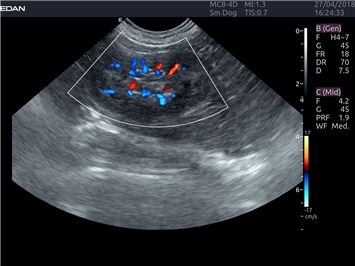

EDAN Acclarix LX4 VET

EDAN Acclarix LX4 VET представляет собой профессиональную ультразвуковую систему, специально разработанную для ветеринарных исследований. Сочетание стабильности, высокой производительности и эффективности делает эту систему идеальным выбором для современной ветеринарной практики.

Трехмерная реконструкция ЦДК:

Да

Энергетический допплер:

Цветовой допплер: